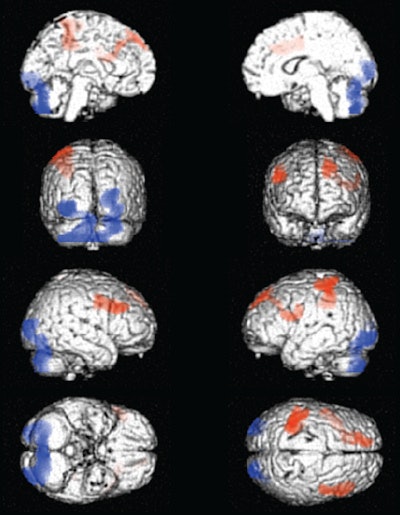

Ferrando and colleagues found that active users generally showed hypoperfusion, or decreased blood flow, in the mesial frontal, anterior cingulate, medial orbitofrontal, thalamic, and midbrain regions. Abstinent subjects showed hypoperfusion in the right temporal, medial orbitofrontal, midbrain, and cerebellar regions.

Active users also generally showed cerebellar hyperactivity, whereas those abstaining from cocaine use had left frontoparietal hyperactivity.

In the comparison of abstinent (left) and active (right) cocaine users, SPECT images showed areas of increased (red) and decreased (blue) perfusion. Image courtesy of Dr. Rodolfo Ferrando.There was an apparent reversal of brain dysfunction in the prefrontal cortex of now-abstinent cocaine users, according to the researchers. Compared with active users, the abstainers showed increased perfusion in the dorsolateral frontal and left parietal areas of the brain, but also decreased perfusion in the posterior occipital cortex and in the cerebellum.

The partial reversal of dysfunction in the abstinent cocaine users "may reflect an improvement in limbic balance, emotional control, and adapted behavior that is seen in abstinence subjects compared to active users," Ferrando and colleagues wrote.

"Improvement of frontal function may place the subjects in a better position to decide what is best for themselves and their future over the immediate reward the drugs can offer," Ferrando said. "In other words, these images show how the brain of the abstinent subject can gradually retrieve the necessary tools to stay away from drugs."